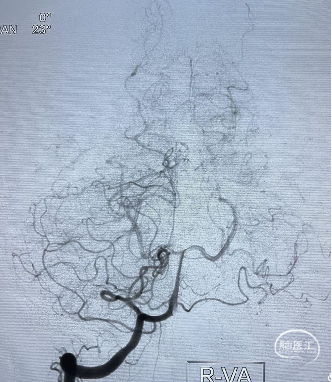

![]() 术后影像

术后影像

术后多角度造影显示动脉瘤致密填塞,其他血管显影正常。术后CT无异常,mRS 0 分。

术后CT未见异常,mRS 0 分,无神经系统症状和体征,计划术后半年后复查DSA